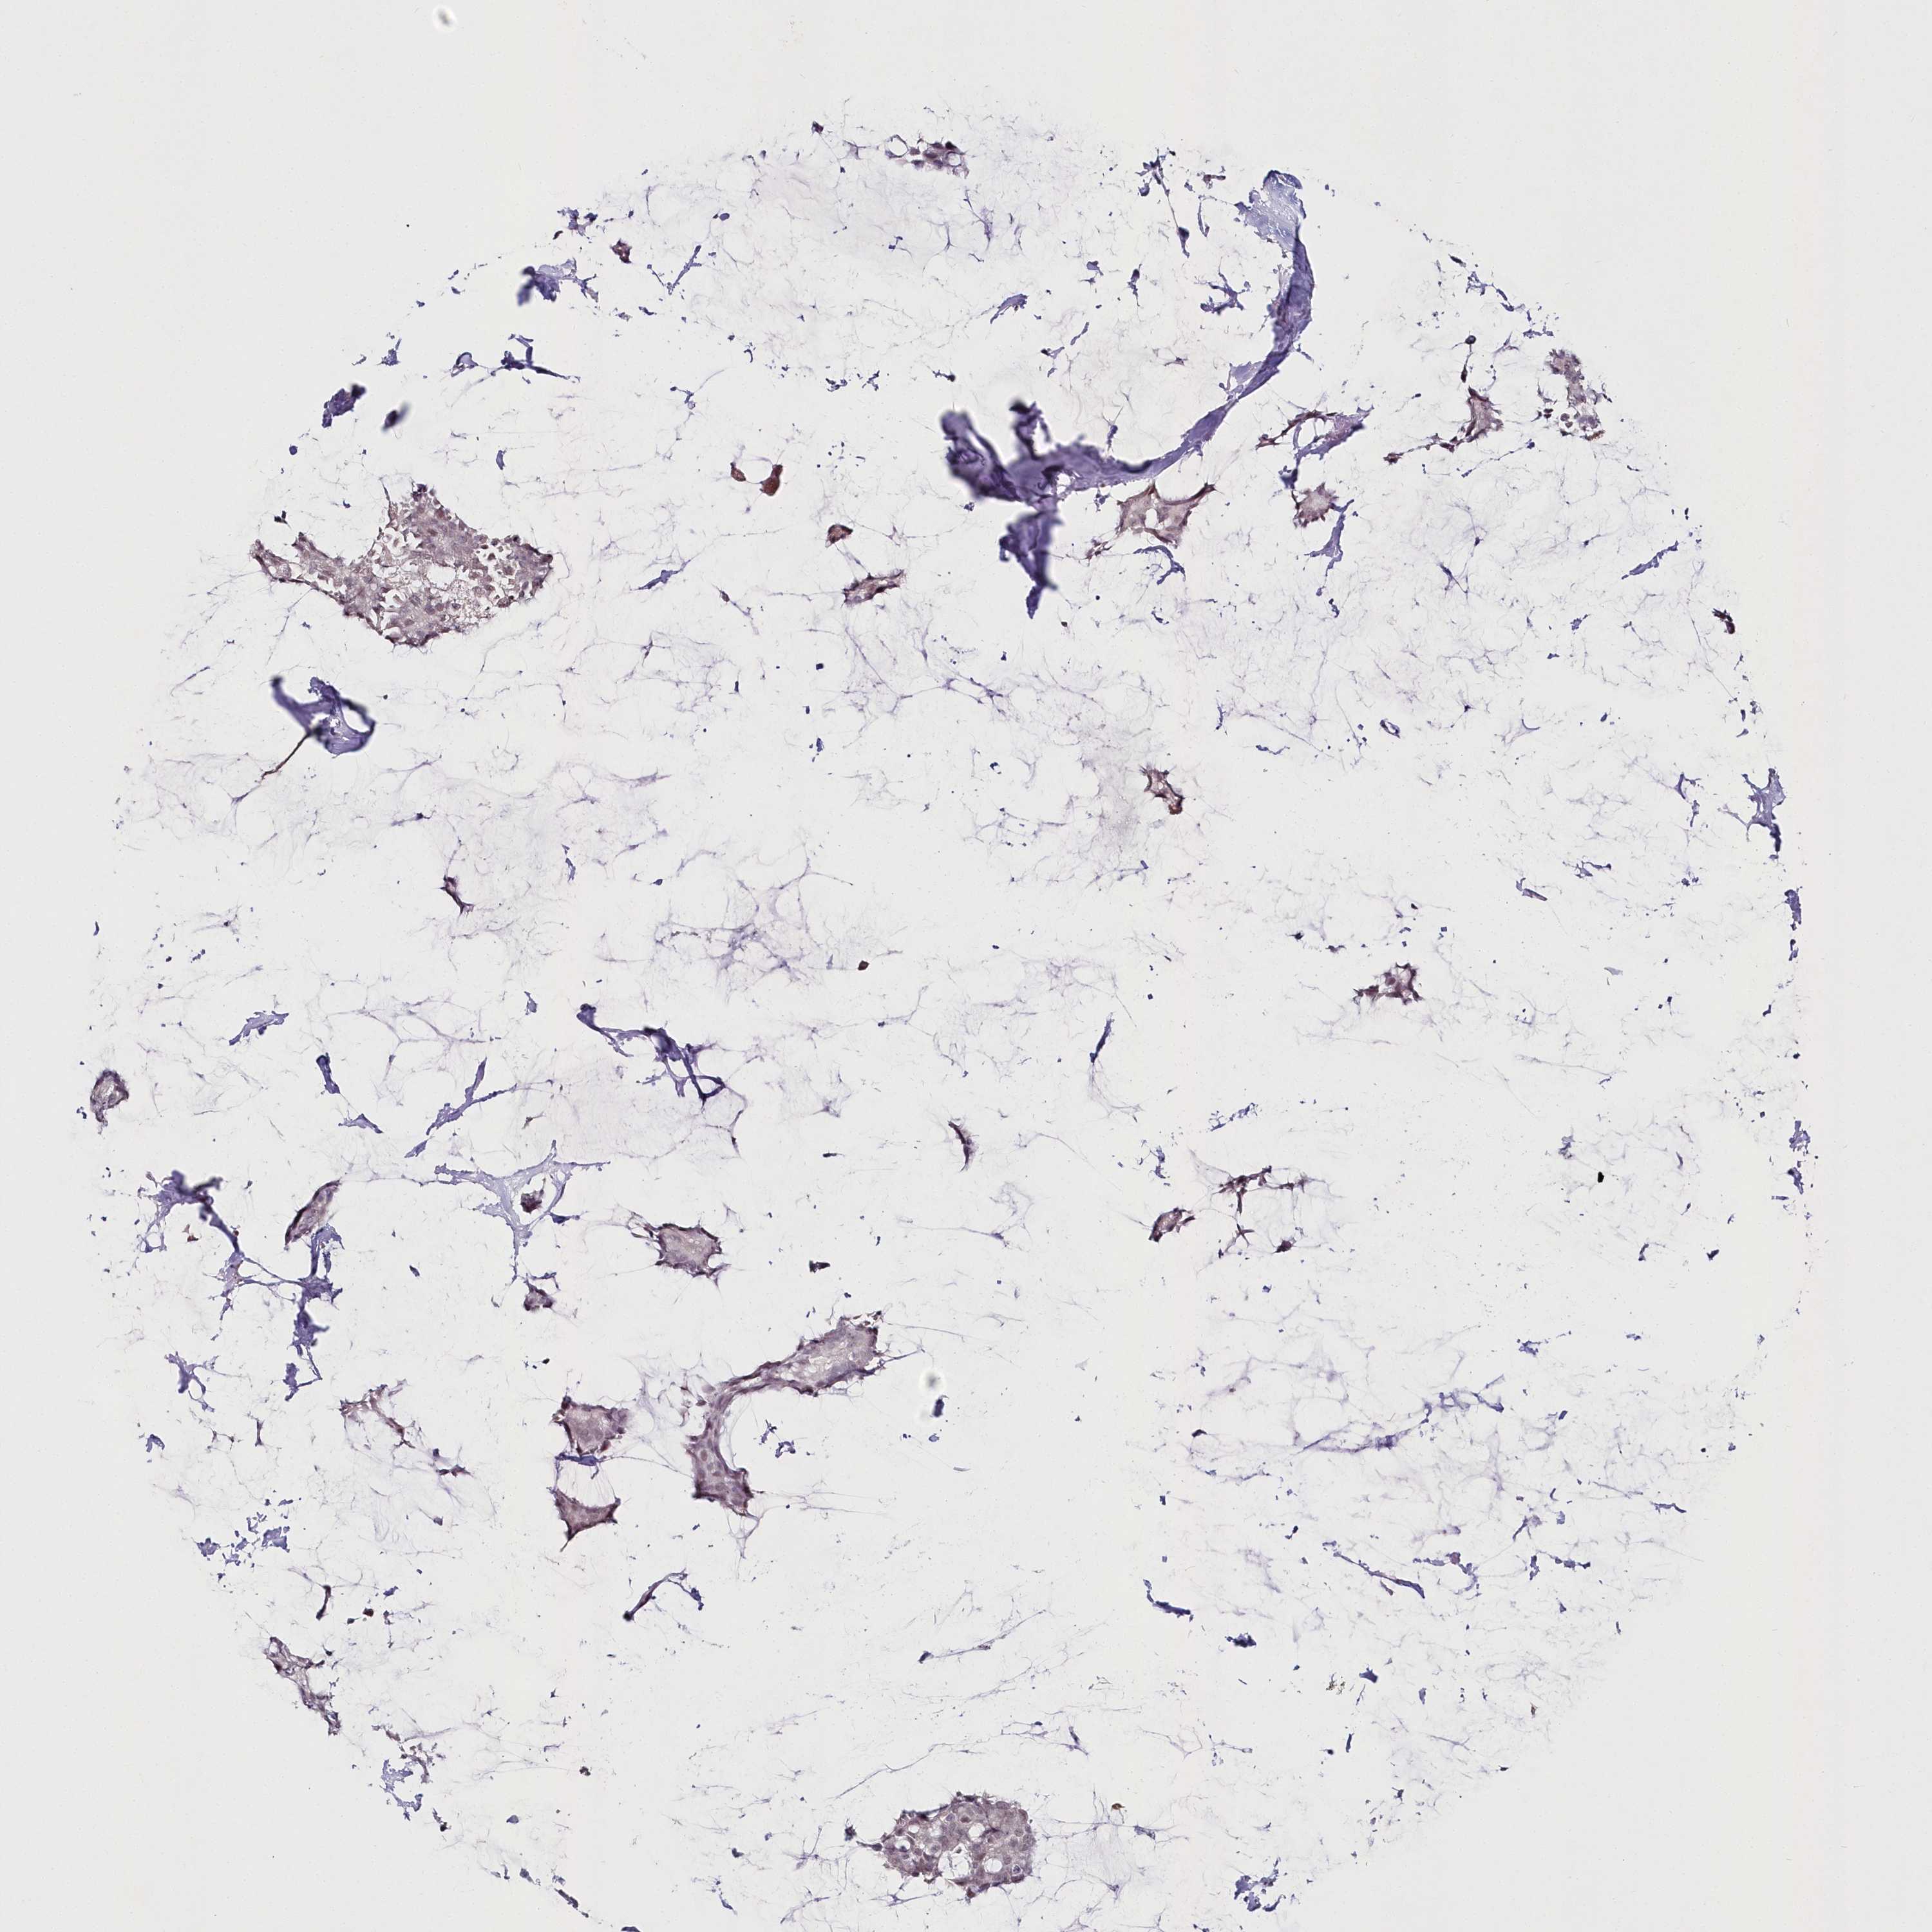

CANCER BREAST CANCER Show tissue menu

BRCA TCGA BRCA VALIDATION PROTEIN EXPRESSION